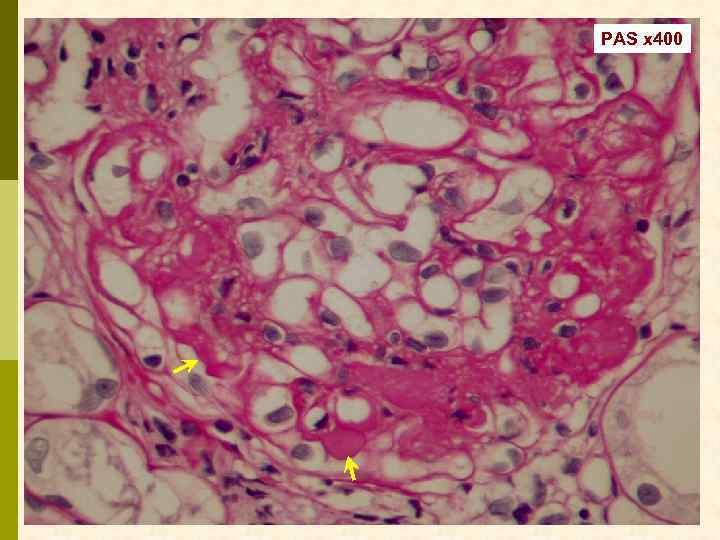

Б. Клинический случай № 21631 Александр К. , 1972 г. рожд. В 1999 г. выявлен гепатит С, в 2003 г. – ВИЧ. С июня 2006 г. – отеки, быстрое развитие анасарки. Почки по УЗИ 13 7 см. Протеинурия 9, 6 г/сут, креатинин 0, 19 мм/л, холестерин 18 мм/л. Обнаружен Ig. M-криоглобулин. 02. 11. 2006 - диагностическая нефробиопсия.

PAS x 100

Masson x 100

Masson x 100

Jones x 100

Jones x 100

PAS x 400

PAS x 400

Jones x 400

Jones x 400

Masson x 400

Masson x 400

Masson x 400

Иммунофлюоресцентное исследование: p Клубочки: Ig. G (2+), Ig. M (3+), C 3 (2+), kappa (3+), lambda (1 -2+) - диффузная, субэндотелиальная и интракапиллярная, крупно-гранулярная экспрессия; p Стенки артериол: C 3 (2+); p Цилиндры: Ig. G (2+), Ig. A (3+), Ig. M (2+), C 3 (3+), kappa (3+), lambda (2+); p Реабсорбированные белковые капли: kappa (3+).

Предварительное гистологическое заключение: p Мембрано-пролиферативный, HCV-ассоциированный, криоглобулинемический(? ) гломерулонефрит с полным склерозом 47% клубочков, сегментарным склерозом 22% клубочков и формированием полулуний в 15% клубочков; p диффузно-очаговый выраженный острый канальцевый некроз; p выраженный артерио-артериолосклероз. Примечание: Криоглобулинемическая природа поражения будет уточняться при ЭМ-исследовании.

Заключение p Мембрано-пролиферативный гломерулонефрит, криоглобулинемический, ВИЧ-ассоциированный, на фоне гепатита С